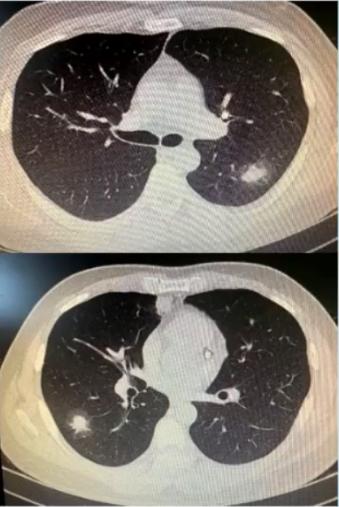

病例2

男性,33岁,既往身体健康,发热6天入院,无咳嗽、咳痰、咯血、呼吸困难。

日最高体温38.4℃,伴头痛、全身乏力,肺CT示双肺多发结节影,予头孢克肟、美洛西林舒巴坦、布洛芬、奥司他韦等治疗效果欠佳。

血常规WBC 10.63 G/L,N 0.816,L 0.101。CRP 7.42mg/dl,肺炎支原体抗体<1:40,SARS-CoV-2核酸及抗原筛查试验(-)。

入院后情况

• 肺炎支原体抗体1:320

• 左氧氟沙星0.5 QD 口服治疗后体温正常

图2 影像表现以多发肺结节合并晕征,类似于真菌感染